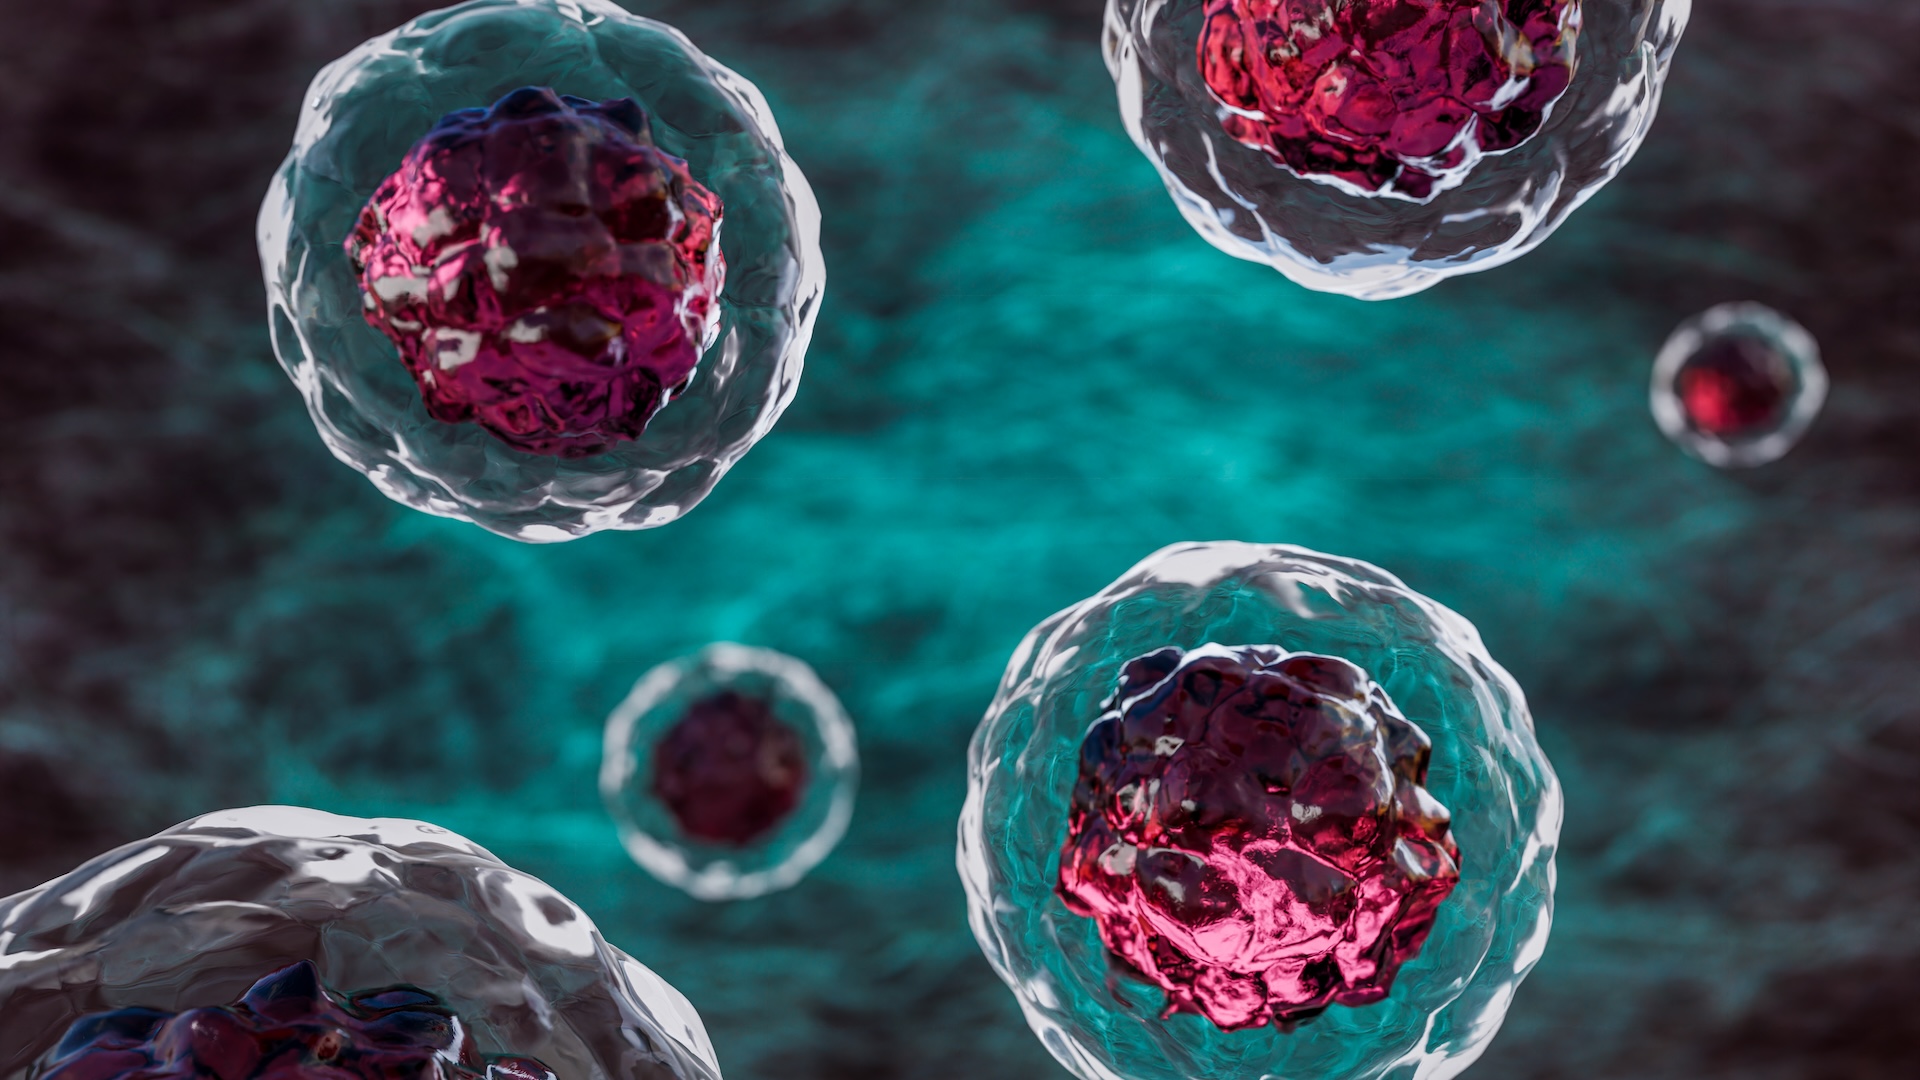

Slaying zombie cells could treat diabetes

(Image credit: OsakaWayne Studios via Getty Images)

Slaying zombies isn’t just for horror movie and video game protagonists, it could offer scientists a key method for treating diabetes, Live Science contributor Elise Ceyral writes.

A new study has revealed that killing senescent, or “zombified”, cells inside the blood vessels of mice reduced their fat mass, improved their blood sugar levels, and decreased their metabolic dysfunction. And the research could pave the way for new treatments that improve cardiovascular health more generally, scientists say.

You can read the full story here.